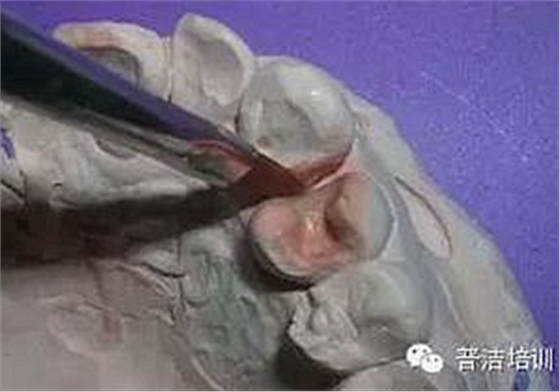

左上4近中鄰 牙合 面齲,3 4之間與對頜牙的牙尖形成咬牙合接觸。從3的磨耗程度可以看出4的近中牙合面受力也很大,單純充填可能不長久。決定用金屬嵌體修復(fù),但患者對美觀比較在意,瓷又有點貴,最后選擇樹脂嵌體

釉質(zhì)鑿制備“明尼蘇達溝”,增加固位

鄰面預(yù)備到自潔區(qū),齦壁盡量在齦上,齦壁下方距鄰牙之間要有0.6MM左右的間隙,以保證硅橡膠強度,因樹脂強度稍差,峽部預(yù)備比金屬要稍寬一點